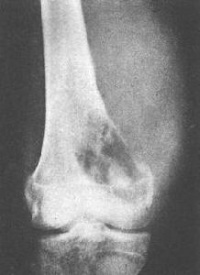

X线表现为骨性病损自干骺端突出,一般比临床所见的要小,因软骨帽和滑囊不显影,肿瘤的骨质影像与其所在部位干骺端的骨质结构完全相同。不易区别。位于长骨的肿瘤其生长方向与邻近肌肉牵引的方向一致,例如股骨远端的骨软骨瘤向股骨的生长,胫骨近端的肿瘤向胫骨远端生长。其形状不一,可有一个很长的蒂和狭窄的基底。或很短粗呈广阔的基底,较大的肿瘤其顶端膨大如菜花,悬垂状骨性骨块,其尖端朝向邻近关节相反方向。其基底直接或有一细蒂与骨皮质相连续。瘤体表面的软骨帽虽然在X线上不显影,但常有钙化和骨化位于前臂小腿的较大肿瘤可压迫邻近骨骼,产生压迫性骨缺损或畸形。多发性者往往合并骨骼畸形。

1.X线表现:表现为附着于干骺端的向外骨性突起,生长方向与肌肉的牵引方向一致,与受累骨皮质和松质骨相连,软骨帽不显影,有长蒂型和广基型之分。